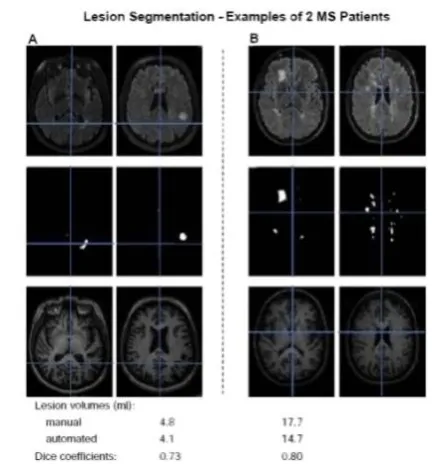

München, 20.12.2011 – Forscher des Krankheitsbezogenen Kompetenznetzes Multiple Sklerose (KKNMS) haben einen Algorithmus entwickelt, mit dem MRT-Bilder von MS-Patienten automatisch nach Läsionen gescreent werden können. „Unser Ansatz spart nicht nur Kosten und Zeit, sondern ist außerdem genauer als die herkömmliche manuelle Auswertung“, erklärt Studienleiter PD Dr. Mark Mühlau, Oberarzt in der Neurologischen Klinik des Klinikums rechts der Isar der Technischen Universität München. Der Algorithmus eignet sich vornehmlich für die Grundlagenforschung und klinische Studien, weil hier in der Regel viele MRT-Bilder und demnach große Datenmengen ausgewertet werden müssen.

Der neu entwickelte Algorithmus ist aktuell für 3 Tesla (3T) MRT-Geräte mit einer dreidimensionalen T1-gewichteten Gradientenecho (GRE) Sequenz und einer konventionellen FLAIR Sequenz konzipiert. Das Studienergebnis hat gezeigt, dass die automatische Bildsegmentation dem manuellen Verfahren in Hinblick auf Sensitivität, Spezifität und Genauigkeit in nichts nachsteht. „Wir gehen sogar so weit zu sagen, dass unser Algorithmus der manuellen Auswertung überlegen ist, da es keine Effekte gibt, die allein auf den jeweiligen auswertenden Radiologen zurückzuführen sind (sogenannte user bias)“, meint Mühlau.